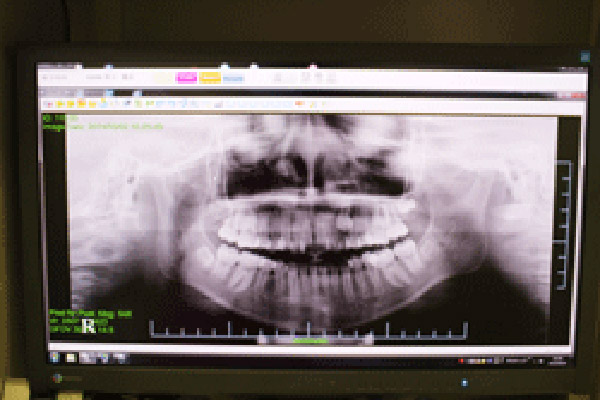

デジタルレントゲン

身体への負担を最小限に抑えた、スピーディーで鮮明な撮影

当院導入のデジタルレントゲンは、高感度のセンサーを使用することで、従来のフィルム式レントゲンに比べて被曝線量を約1/10から1/4程度にまで大幅に低減しています。

また、現像の必要がないため、撮影後すぐに診療台のモニターで画像を確認でき、お待たせする時間がありません。

デジタルデータのため、画像を拡大したりコントラストを調整したりすることが自在にでき、初期の微細な病変の発見にも役立ちます。